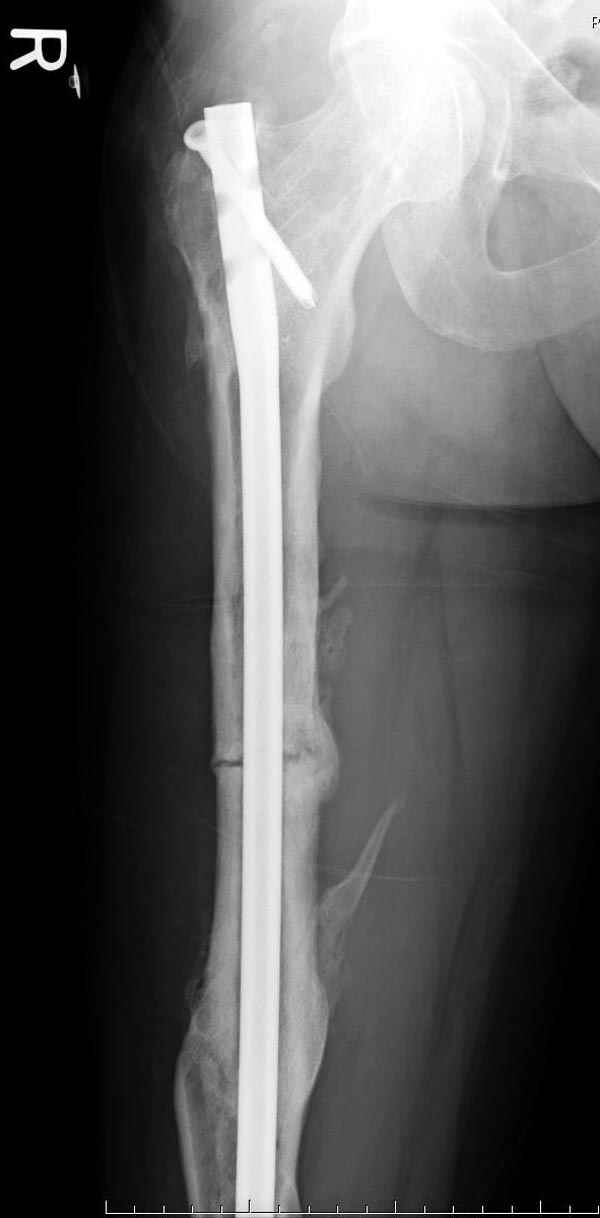

На следующий день произвели интрамедуллярный остеосинтез: этапы во время операции (рис №8, №9)

и последующих снимках (рис №10, 11, 12, 13) перелом сростается и передвигается с полной нагрузкой.